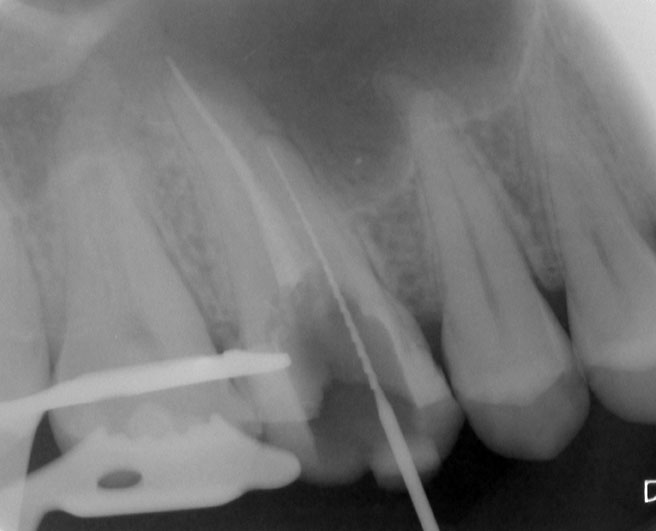

Patient N.M. wünscht eine Drittmeinung, zwischenzeitlich hatte er bereits einen zweiten Zahnarzt konsultiert. Dieser bestätigte eine insuffiziente Wurzelfüllung und vermutete eine Instrumentenfraktur im mb1 (Abb. 1).

Abb. 1: Ausgangsröntgenbild des insuffizient gefüllten Zahnes 16.

Röntgenbefund

Mittels Röntgenaufnahme lässt sich ein frakturiertes Instrument in mb1 vermuten. Des Weiteren scheint es, als sei der distale Wurzelkanal sowie der mb2 nicht abgefüllt worden, was sich zu einem späteren Zeitpunkt der Behandlung bestätigen sollte. Der Patient wurde vom vorbehandelnden Zahnarzt über die Fraktur nicht aufgeklärt.